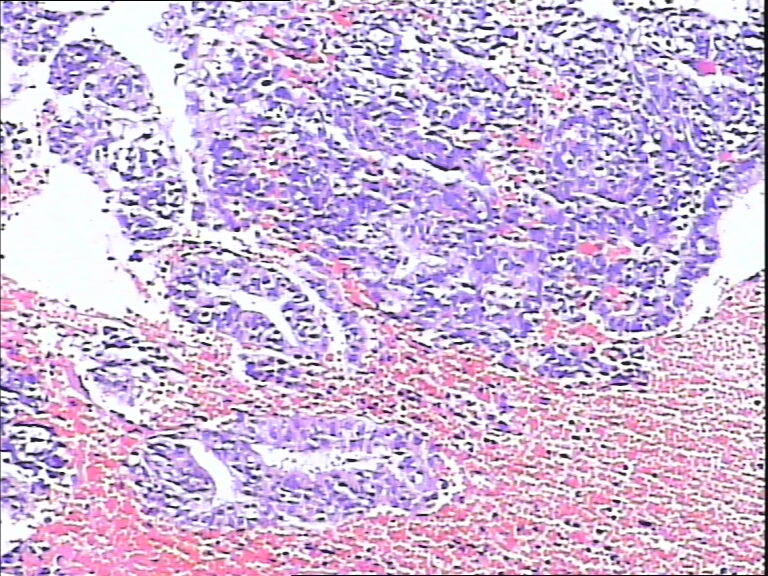

41岁,停经5年再出血。

• 宫内膜图2

图2

流血期子宫内膜,腺体反应不同步。

片子不是很清楚,像是月经期子宫内膜

是不是采图有问题,片子上细胞变形严重,从轮廓看问题不大,至少不是恶性,再传点图

流血期子宫内膜,腺体反应不同步

腺体增生,部分腺上皮有分泌。